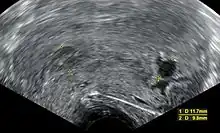

A review article in The New England Journal of Medicine based on a consensus meeting of the Society of Radiologists in Ultrasound in America (SRU) has suggested that miscarriage should be diagnosed only if any of the following criteria are met upon ultrasonography visualisation:[110]

| Crown-rump length of at least 7 mm and no heartbeat. | Crown–rump length of less than 7 mm and no heartbeat. | [110][111] |

| Mean gestational sac diameter of at least 25 mm and no embryo. | Mean gestational sac diameter of 16–24 mm and no embryo. | [110][111] |

| Absence of embryo with heartbeat at least 2 weeks after an ultrasound scan that showed a gestational sac without a yolk sac. | Absence of embryo with heartbeat 7–13 days after an ultrasound scan that showed a gestational sac without a yolk sac. | [110][111] |

| Absence of embryo with heartbeat at least 11 days after an ultrasound scan that showed a gestational sac with a yolk sac. | Absence of embryo with heartbeat 7–10 days after a scan that showed a gestational sac with a yolk sac. | [110][111] |

| Absence of embryo at least 6 weeks after last menstrual period. | [110][111] | |

| Amniotic sac seen adjacent to yolk sac, and with no visible embryo. | [110][111] | |

| Yolk sac of more than 7 mm. | [110][111] | |

| Small gestational sac compared to embryo size (less than 5 mm difference between mean sac diameter and crown-rump length). | [110][111] |